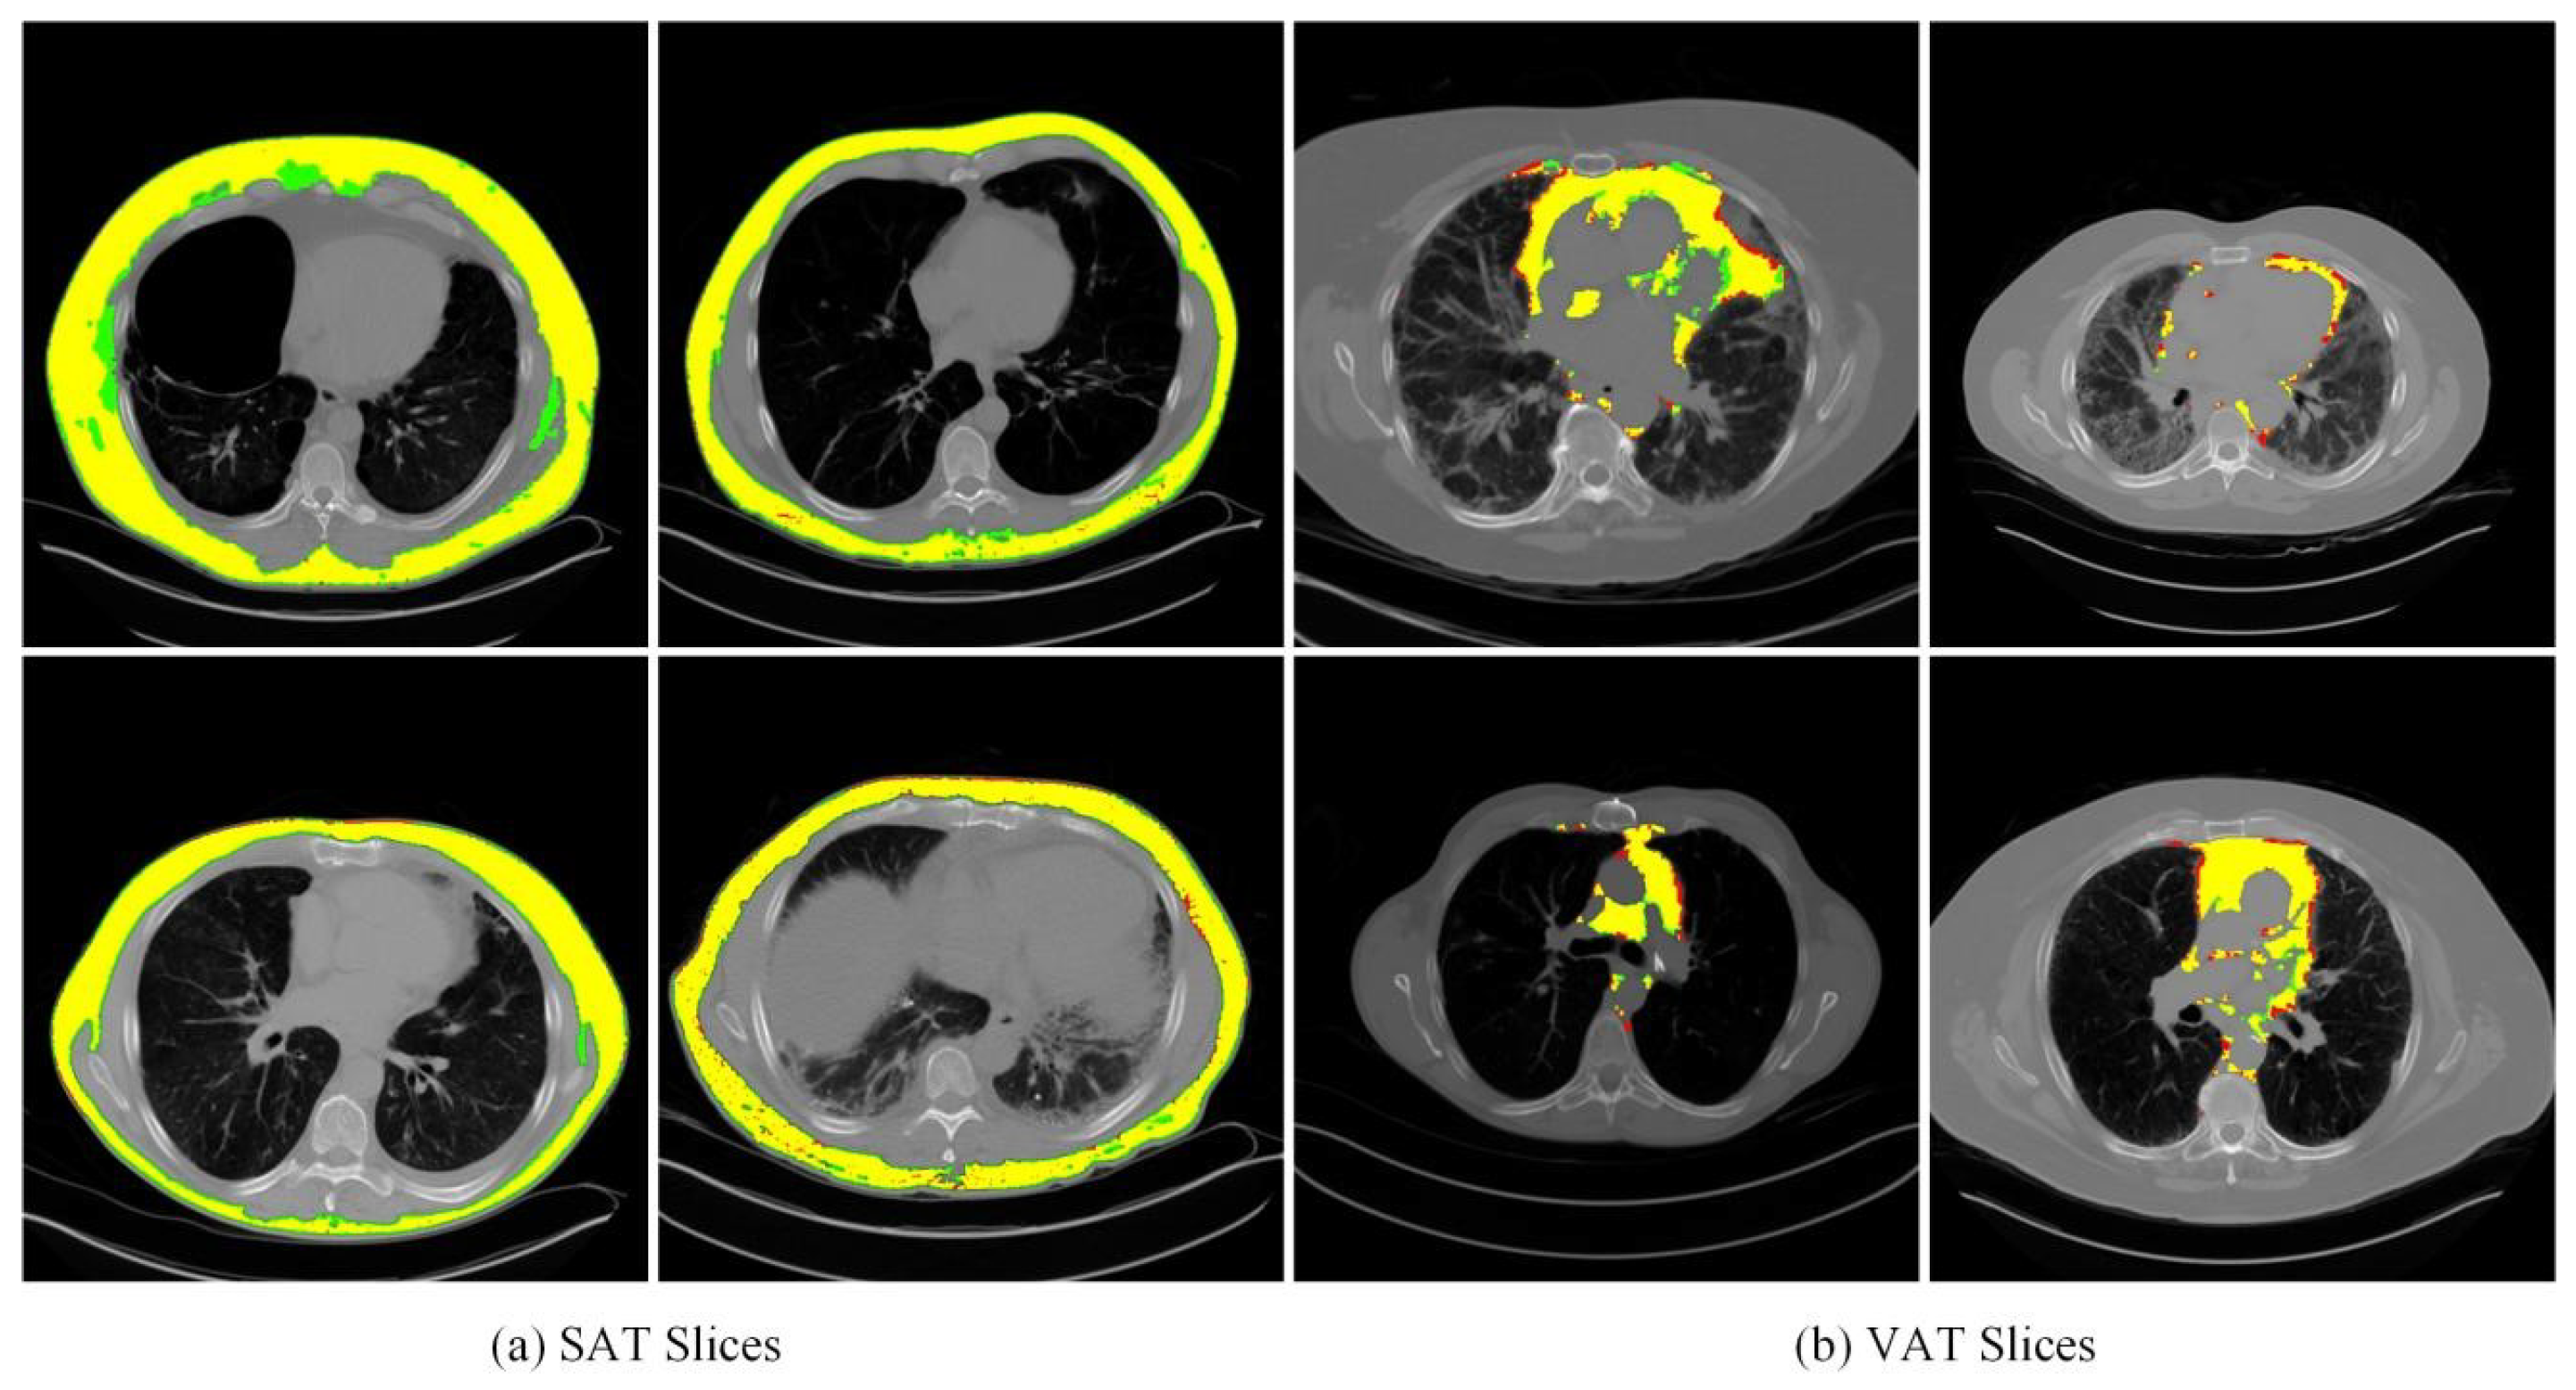

The model applied a four-fold cross-validation to segment SAT and VAT to ensure the results’ reliability and robustness. For that, the averaged overall Precision and Recall rates were computed along with the overall averaged F1 Score and averaged Dice Score for the segmentation accuracy. Some examples of segmented parts and their corresponding ground truth for SAT and VAT are visualized in Figure 8.

Figure 8. Visualizations of segmentation results. Both the segmented parts and ground truth for SAT and VAT are visualized. Green, yellow, and red regions represent the ground truth, true predictions, and false predictions, respectively.

The lung CT slices showed that the adipose tissue had non-uniformity and irregularity, i.e., heterogeneity, while the adipose tissue has a similar morphological profile to fluid in the body. Comparing the prediction and ground truth visually in segmentation demonstrates the significant performance while missing some tiny fat tissues at the edge of the predicted results. The misclassification in the mentioned regions might be because of the blurred border between the pixel intensity of the adjacent area. During the experiment, we adjusted the label of the training set to clean the misclassified parts and screened the CT slices with big noises. This is aimed to ensure the relative purity of the training dataset and exclude the negative influence during the learning process that is not supposed to be there.